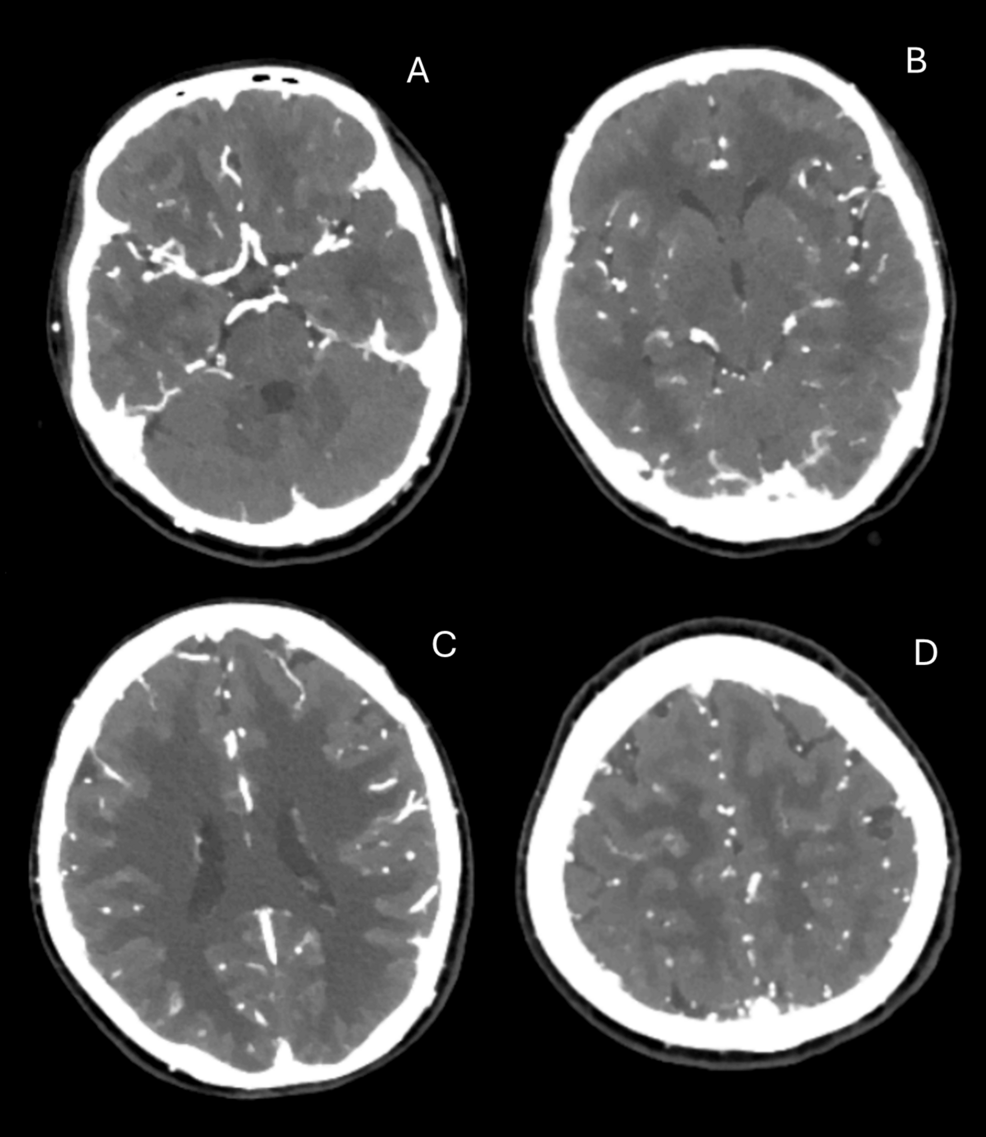

Initial investigations looking for common metabolic or infectious causes revealed only a mild metabolic acidosis on venous blood gas. Laboratory blood tests showed an expectedly elevated urea, mildly raised potassium, and a chronically elevated and stable troponin. A mild neutrophilia was also noted (Table 1). None of these investigations was felt to be abnormal enough to represent a clear cause of her symptoms. A non-contrast CT of the brain, head, and neck angiogram, to rule out structural or vascular causes, was unremarkable (Figure 1A-D).

Figure 1: CT head and neck angiogram

A-D: transverse planes of a CT head and neck angiogram, which were unremarkable and demonstrated no structural or vascular cause for the presentation